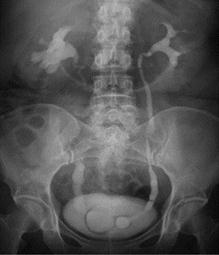

Внутривенная урография – это рентгеновское исследование, которое используется для оценки патологии почек, мочевого пузыря, уретры. Эти структуры составляют мочевые пути. При обычном рентгенологическом исследовании мочевые пути хорошо не визуализируются. Однако при внутривенной урографии в вену вводится контрастное вещество. Контраст попадает в кровоток, концентрируется в почках, выделяется с мочой по мочеточнику.

Контраст блокирует рентгеновские лучи в соответствие со структурой почек, мочеточника, мочевого пузыря, что обнаруживается на рентгеновском снимке как изображение белого цвета.